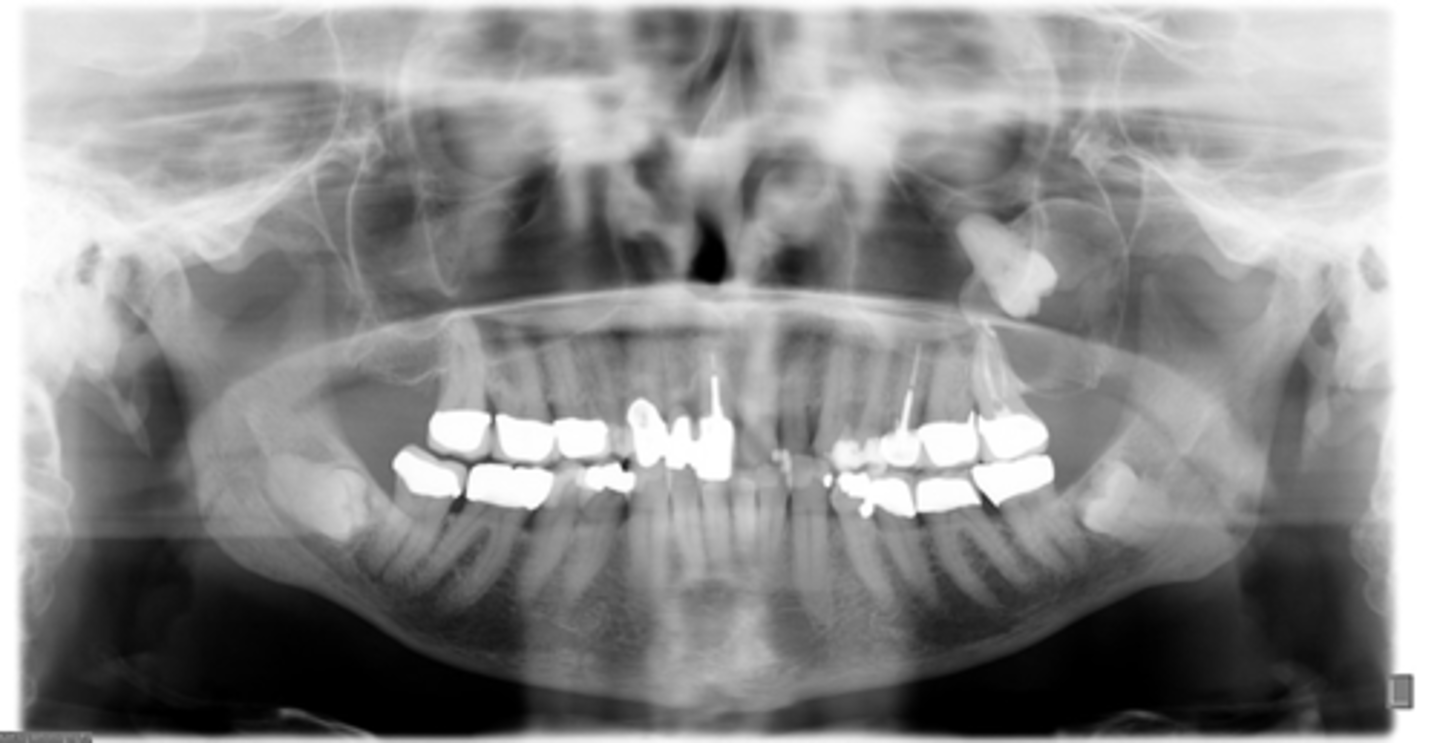

panoramic

what type of imaging is the gold standard for aiding in diagnosis after clinical exam and med history?

You patient presents with a pano exhibiting a well defined, corticated, unilocular radiolucency associated with the crown of an unerupted #16. What type of biopsy should you take first?

- Aspiration

- Cytology

- Incisional

- Excisional